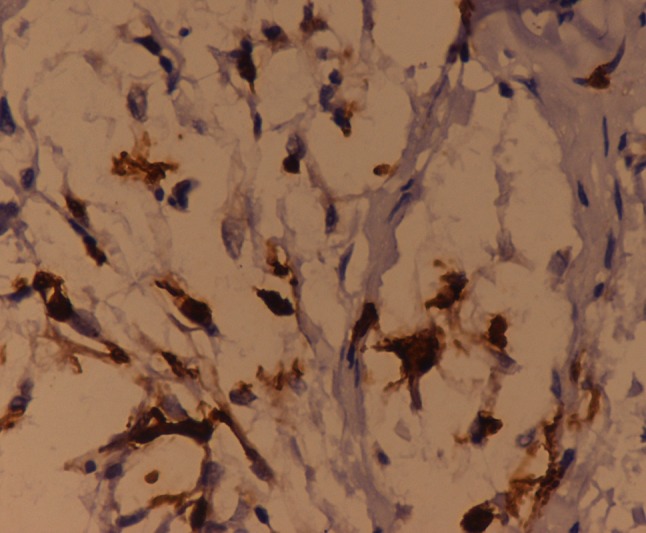

Herein, we report the case of a 16-year-old female who presented to the orthopaedics clinic with the complaint of a painless soft tissue swelling involving the right ankle and foot. She first noted the swelling at about 8 years of age. Initially, it was small, but later, the lesion gradually painlessly progressed to the present size. It completely surrounded the ankle and the heel region. The involved region experienced overgrowth compared to that on the opposite side. The skin over the swelling was normal with no evidence of any discolouration. On palpation, the temperature of the lesion was not raised. The lesion was soft to touch, but it was not possible to distinguish the margins from the adjacent normal area, suggesting an ill-defined lesion. In consistency with the examination findings, the provisional diagnosis of a vascular malformation was considered. The patient was subjected to ultrasonography. It showed an increase in the thickness of the soft tissue, which appeared hyperechoic, comparable to the adjacent normal fat density with multiple interspersed hypoechoic areas within it (Fig. 1). On colour Doppler evaluation, these hypoechoic areas showed slow flow, which it was better to appreciate on power Doppler (Fig. 2). These findings were consistent with the diagnosis of a vascular malformation. However, the duration of the progression of the supposed vascular malformation and the absence of phleboliths on the ultrasound and the subsequent X-ray raised suspicion regarding the diagnosis of a vascular malformation. A second differential of a neurofibroma was considered. Subsequently, a biopsy was conducted. It showed elongated spindle cells with poorly defined, pale eosinophilic cytoplasm and tapering, wavy, or buckled nuclei admixed with a few small nerve fibres (Fig. 3). Immunohistochemistry showed positivity for S-100 (Fig. 4). These findings were consistent with the diagnosis of diffuse neurofibroma.

Fig. 4.

Immunohistochemistry shows diffuse cytoplasmic positivity. IHC S-100 × 40 ×